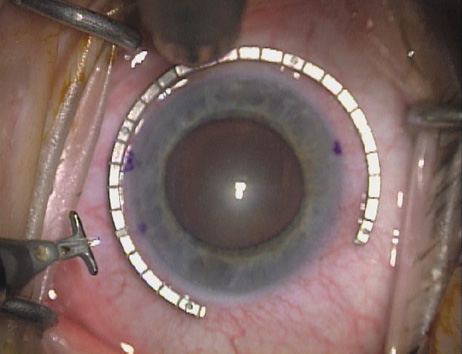

Fig. 11. Opposite relaxing incision is completed. (Reprinted from Hardten DR, Lindstrom RL, Davis EA. Phakic Intraocular Lenses: Principles and Practice. Thorofare, NJ: SLACK Incorporated, 2004, with permission.)

Case 2 is a 79-year-old woman who presented with a very dense left cataract. Her refraction was recorded at −2.25 +2.75 × 125 with a difficult end point. Her manual keratometry and topography measurements were consistent and revealed slightly less than 1.75 D at 120 degrees. Because of the questionable refraction, greater value was placed on the corneal measurements. Based upon the cataract nomogram, the plan was for paired LRIs of 40 degrees to be placed over the steep 120-degree axis (Figs. 1219).

Fig. 12. In this left eye, the steep meridian is at the 120-degree axis and has been delineated by opposing limbal marks. The upper left hand ink mark represents the 6:00 position for orientation. (Reprinted from Hardten DR, Lindstrom RL, Davis EA. Phakic Intraocular Lenses: Principles and Practice. Thorofare, NJ: SLACK Incorporated, 2004, with permission.)